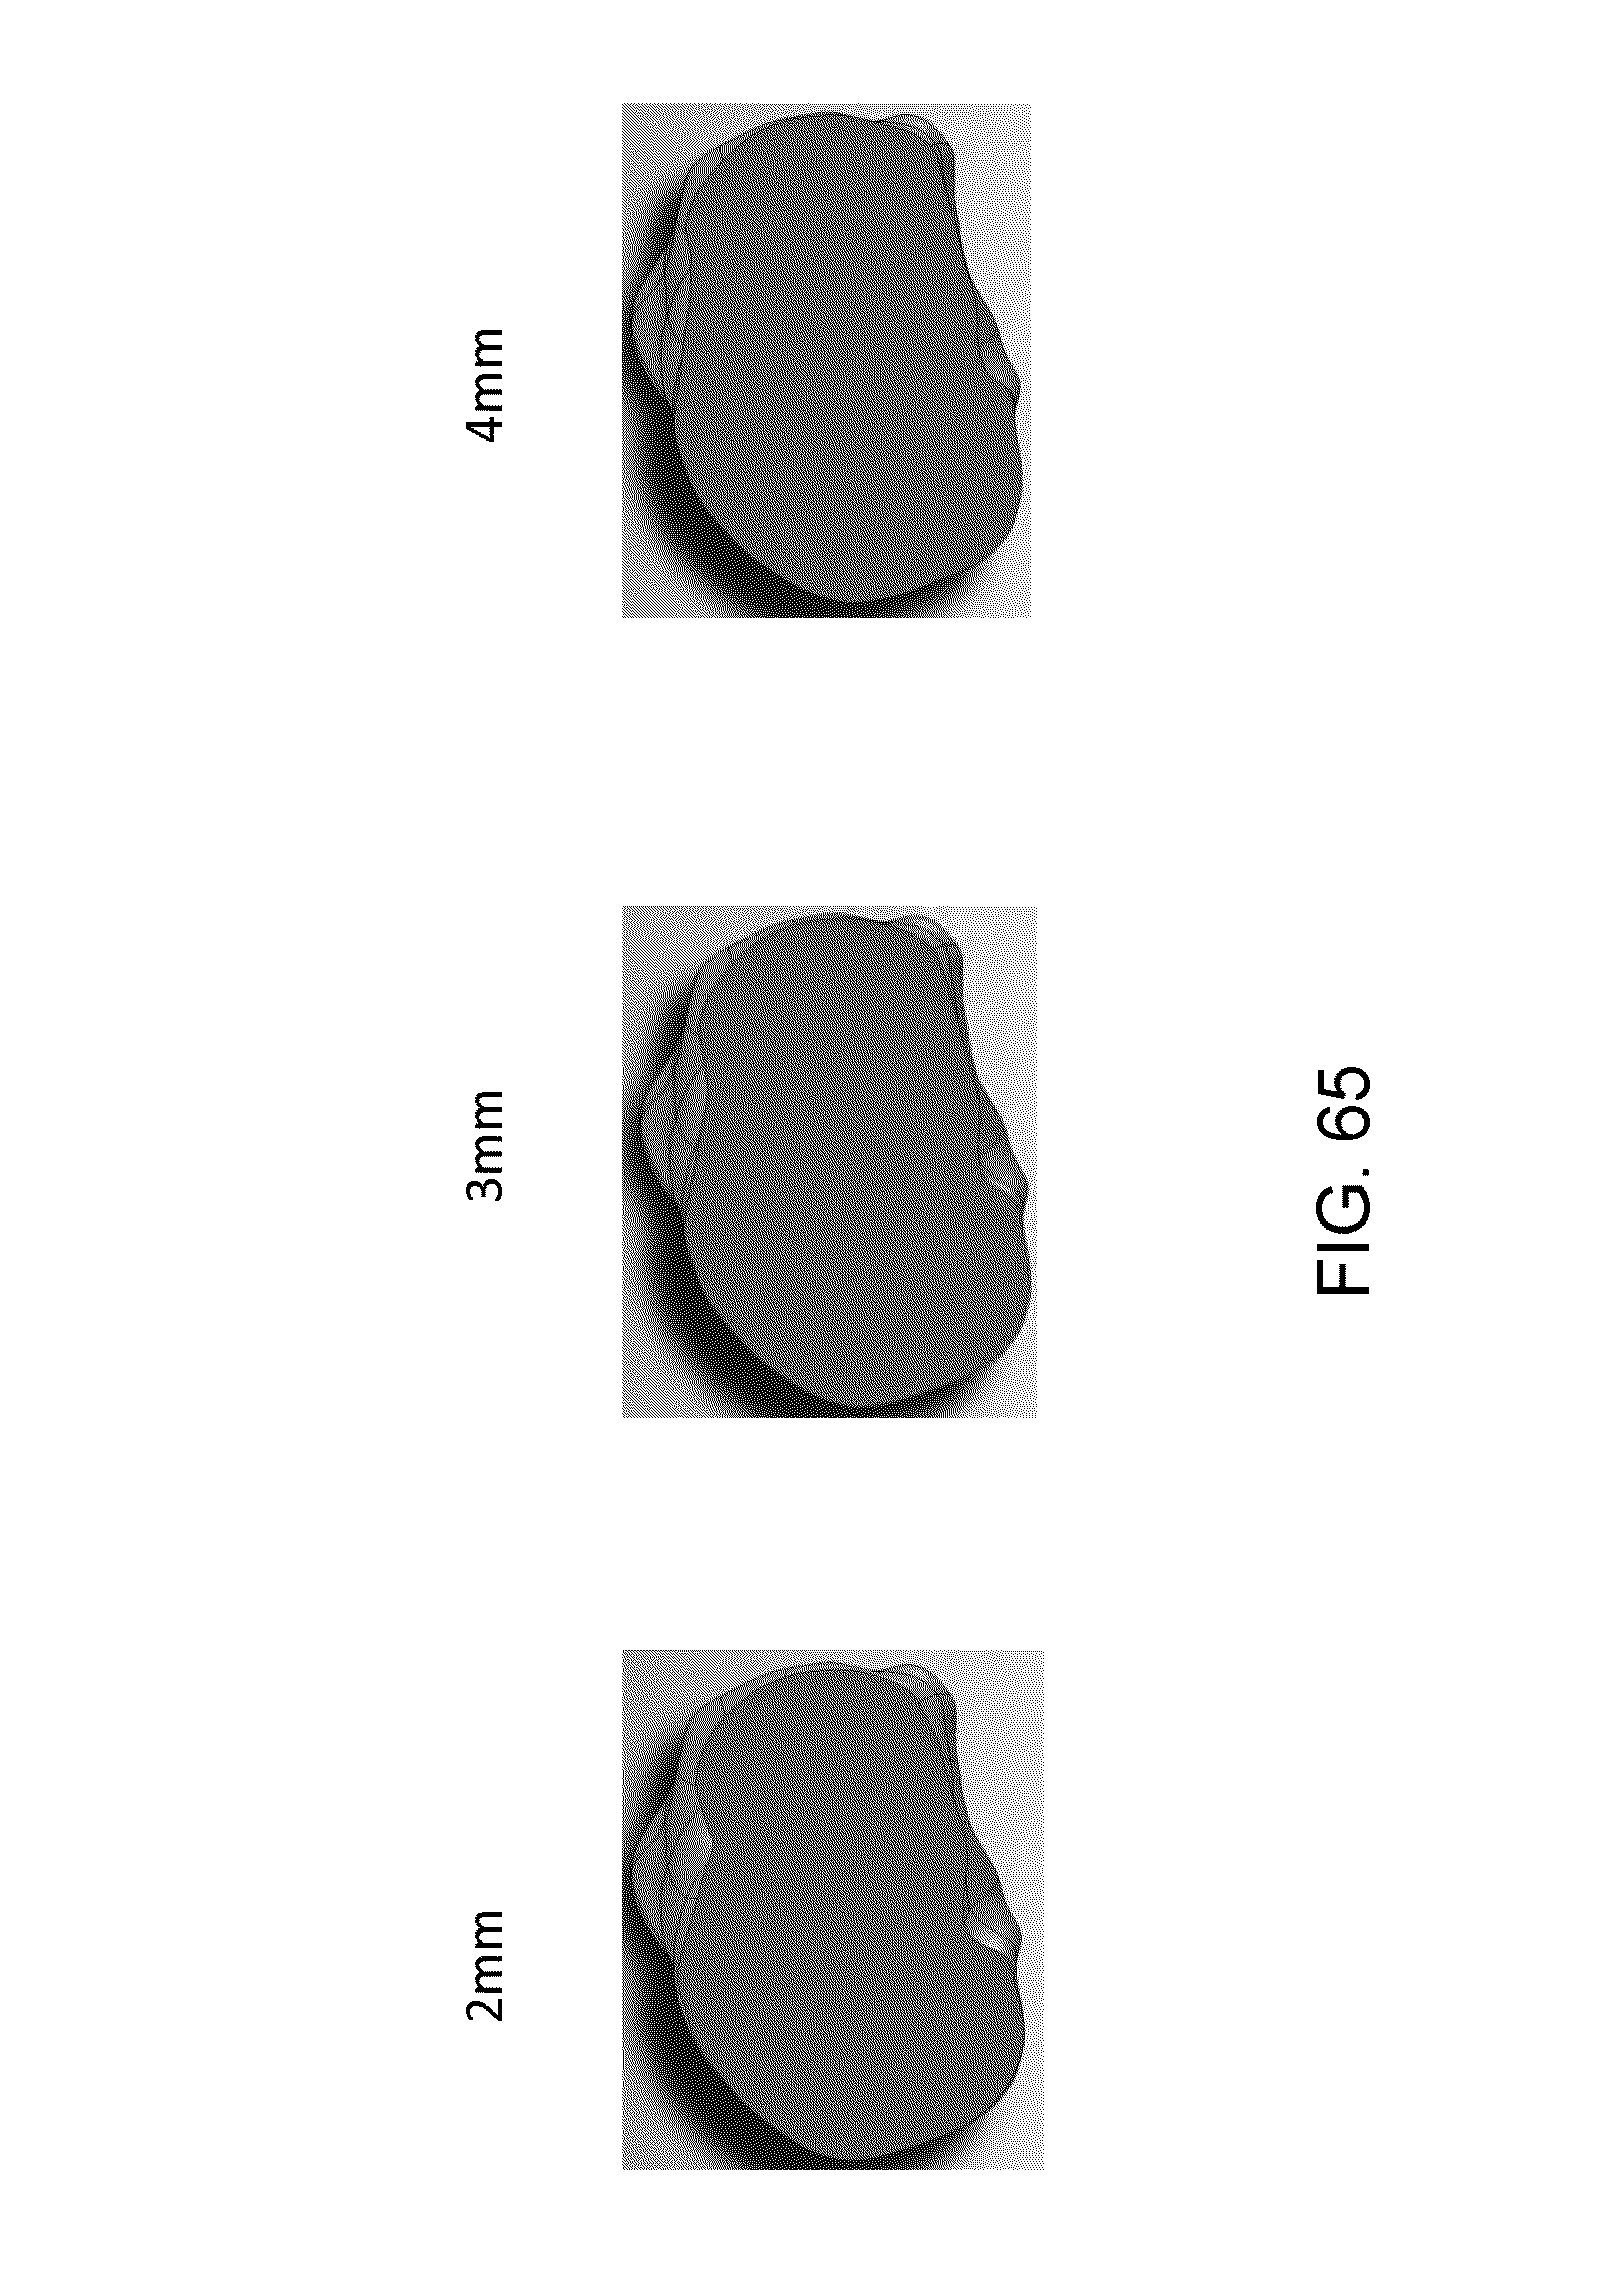

FIG. 65 shows proximal tibial resection cut depths of 2 mm, 3 mm and 4 mm;